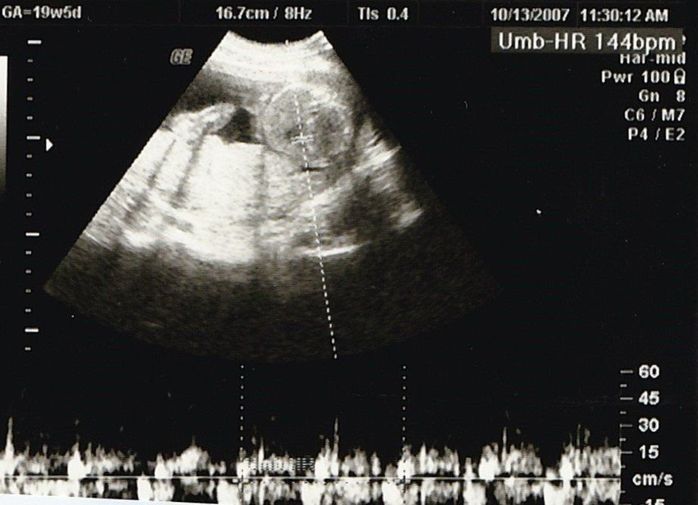

妊娠19週目のエコー写真

安定期に入り、検診のたびに体重や血圧を測るようになりました。前回の検診時から、8~10kgの増加が目安と言われていましたが、妊娠15週から19週の間ですでに1.3kg増。強い食欲と眠気に勝てない毎日に危機感が募り、マタニティーヨガ、マタニティービクスを開始しました。